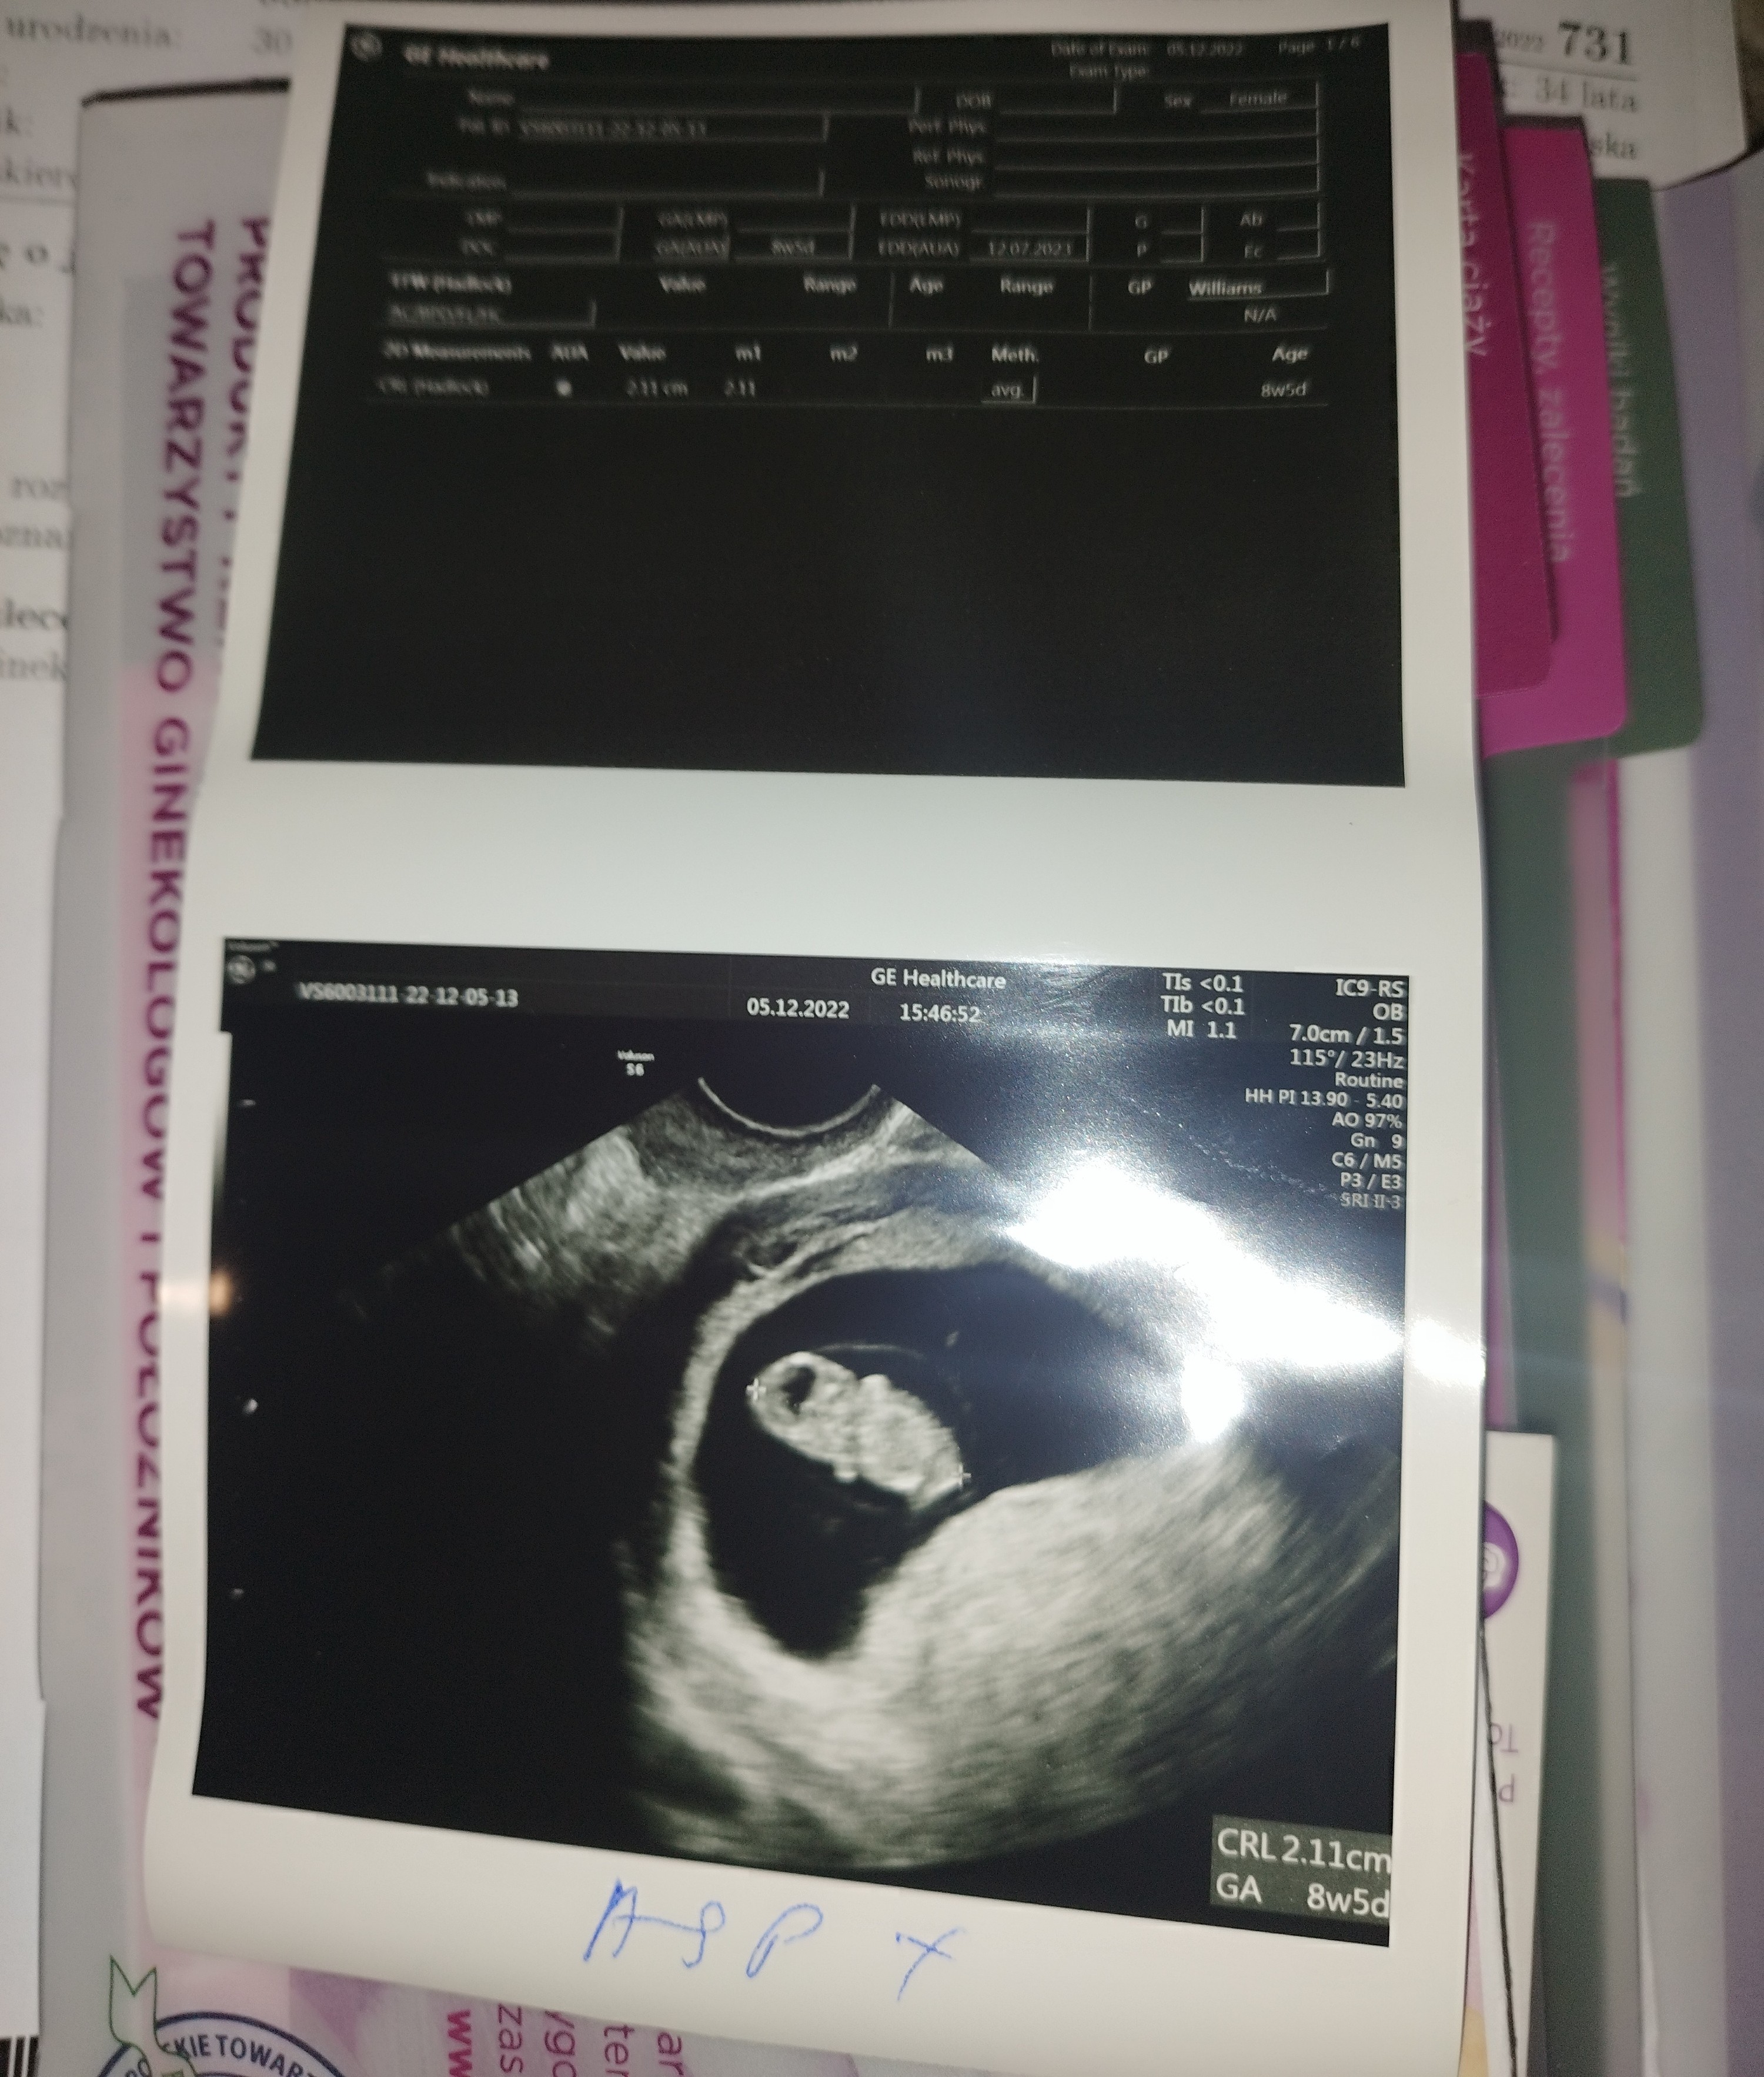

Najpiękniejsze cudo świataŻeby nie było chwalę sięserduszka jeszcze nie słyszałam ale lekarz mówi że jest wszystko dobrze